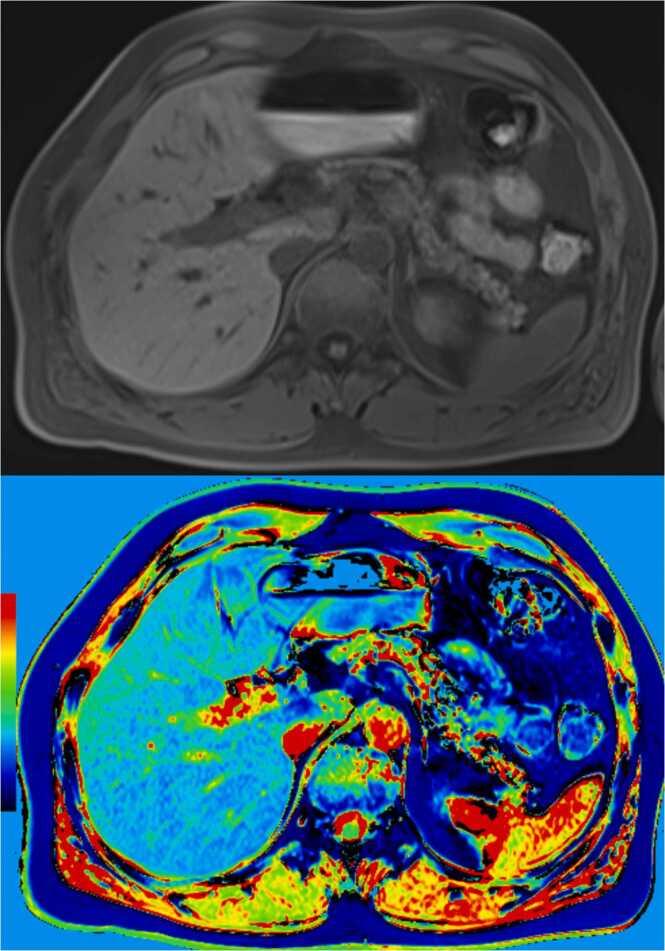

Conventional T1- and T2-weighted magnetic resonance imaging (MRI) of the pancreas can vary significantly due to factors such as scanner differences and pulse sequence variations. This review explores T1 and T2 mapping techniques, modern MRI methods providing quantitative information about tissue relaxation times. Various T1 and T2 mapping pulse sequences are currently under investigation. Clinical and research applications of T1 and T2 mapping in the pancreas include their correlation with fibrosis, inflammation, and neoplasms. In chronic pancreatitis, T1 mapping and extracellular volume (ECV) quantification demonstrate potential as biomarkers, aiding in early diagnosis and classification. T1 mapping also shows promise in evaluating pancreatic exocrine function and detecting glucose metabolism disorders. T2* mapping is valuable in quantifying pancreatic iron, offering insights into conditions like thalassemia major. However, challenges persist, such as the lack of consensus on optimal sequences and normal values for healthy pancreas relaxometry. Large-scale studies are needed for validation, and improvements in mapping sequences are essential for widespread clinical integration. The future holds potential for mixed qualitative and quantitative models, extending the applications of relaxometry techniques to various pancreatic lesions and enhancing routine MRI protocols for pancreatic pathology diagnosis and prognosis.